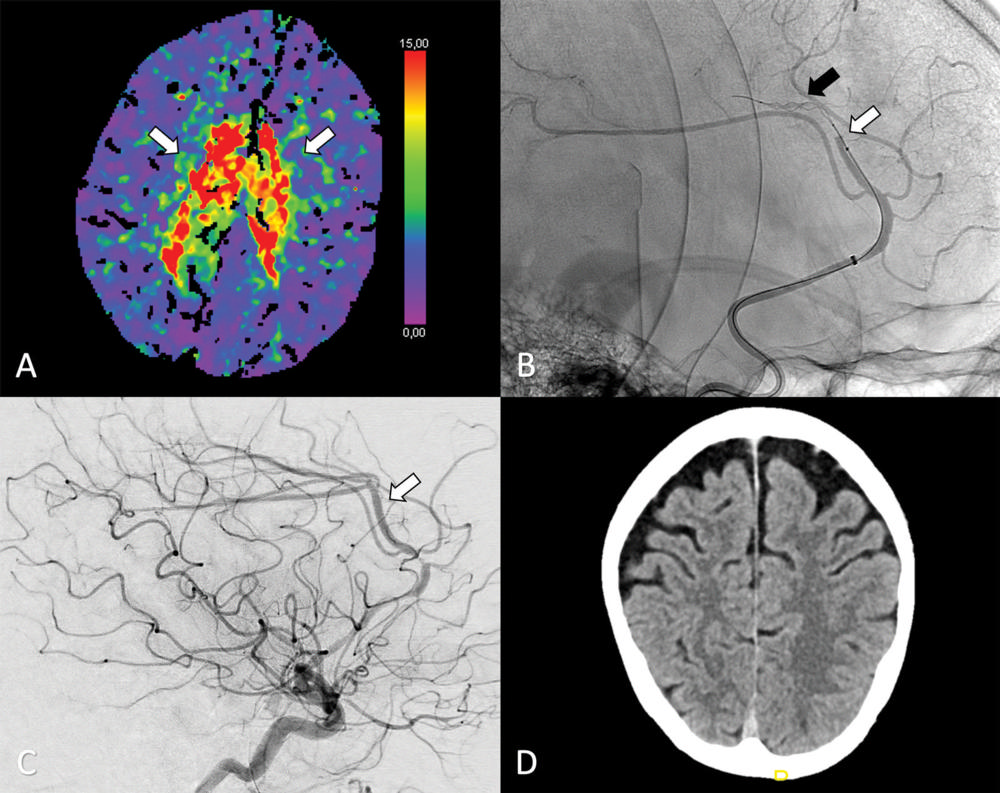

Figure 2. (A–C) Axial perfusion CT (time-to-maximum, < seconds)="" at="" admission="" shows="" a="" bilateral="" deficit="" (arrows="" in="">A) in the territory of the anterior cerebral artery (ACA; ie, azygos variant) because of a distal occlusion of the A3 segment (white arrow, sagittal view in B). Stent retriever thrombectomy (black arrow, sagital view in B) was performed with full reperfusion shown on the final digital subtraction angiography image (arrow, sagittal view in C). (D) Follow-up at 24 hours shows no sign of infarction in the ACA on the axial contrast-unenhanced CT image.